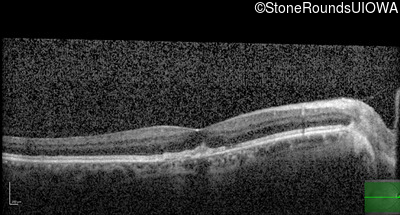

Optical Coherence Tomography - Right - 20/25

Exemplar / OCT Stack

Optical Coherence Tomography - Left - 20/40 -1